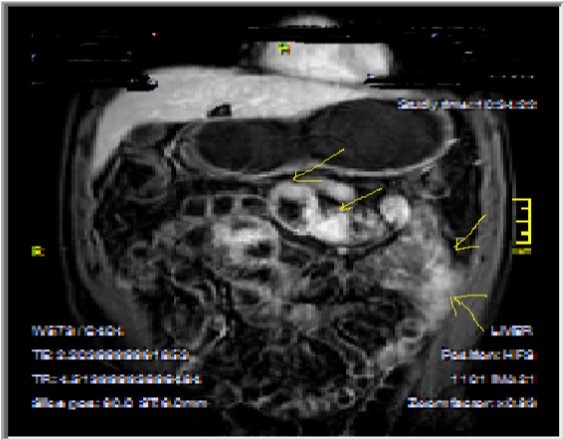

Figure 3a-3b-3c.Diffuse mucosal involvement and extreme luminal narrowing in the terminal ileum due to Crohn’s disease on T2W coronal sequence after OCA administration, stricture and string sign near ileo-ceccal valve in Figure 3b.